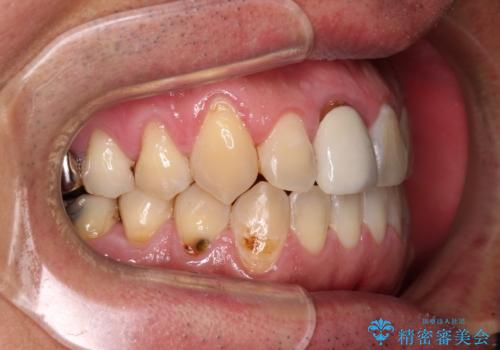

前歯のデコボコとクロスバイトをインビザライン矯正で改善

- 前歯のデコボコと上下のクロスバイトを気にして来院された患者様です。

インビザラインを用い、IPR(歯と歯の間を削る)と歯列全体を拡大させることで、歯並びを整えていくこととしました。

上の前歯が下の前歯を乗り越える際、奥歯がほとんど咬めない時期があり、乗り越えた後も、インビザライン特有の奥歯の咬みにくさが続きました。

咬み合わせ改善のために治療期間を要しましたが、最終的に奥歯はしっかりと咬めるようになりました